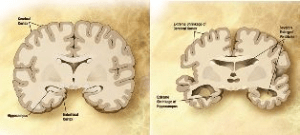

Vergleich eines gesunden und eines mit Alzheimer erkrankten Gehirns (Foto: wikicommons)

Die unheilbare Alzheimer-Krankheit befällt meist Menschen jenseits der 65 und geht mit Gedächtnisverlust und einem Absterben von Gehirnzellen einher. Dabei spielt der nachlassende Austausch zwischen Nervenzellen und dem Gehirn aufgrund der dafür notwendigen, absterbenden Proteine die entscheidende Rolle. Die Produktion eben dieser Proteine wird durch intellektuelle Stimulation und körperliche Aktivtät angekurbelt.